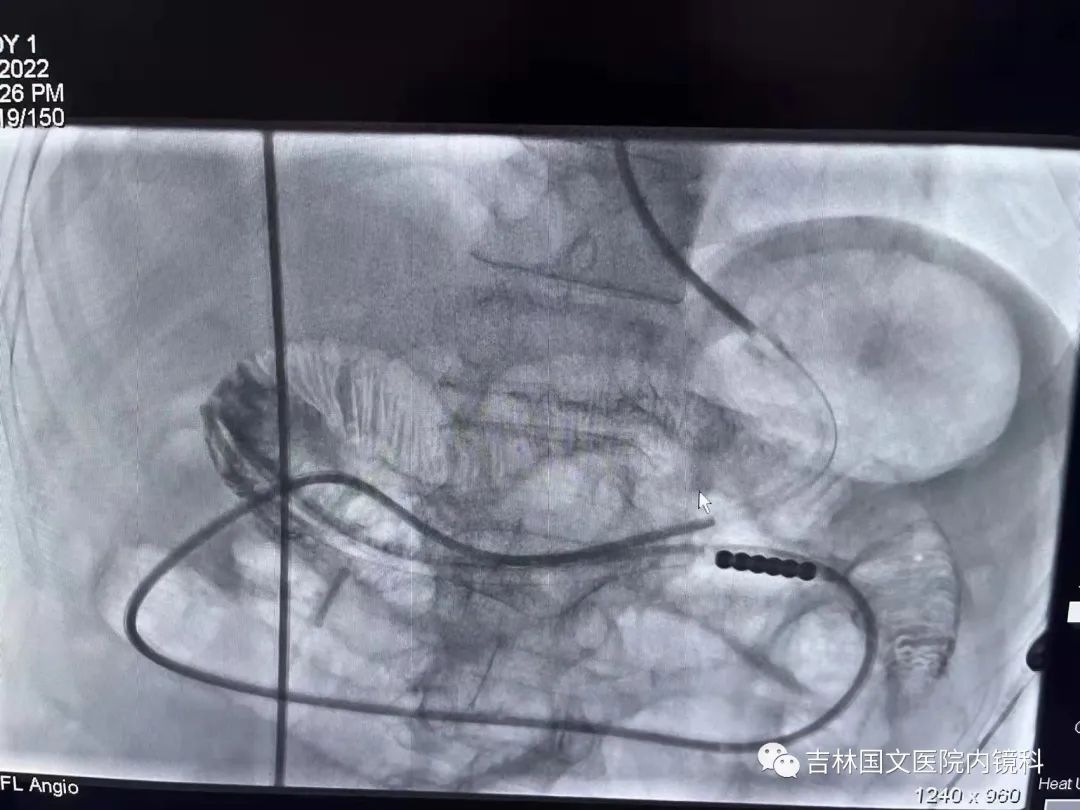

腸梗阻導(dǎo)管置入

這是一位胃術(shù)后的患者,也就是說(shuō)胃內(nèi)許多正常的解剖結(jié)構(gòu)都已經(jīng)切除,這就會(huì)造成腸梗阻導(dǎo)管易迷失方向,猜測(cè)哪邊才是真正的出口是這次操作成功的關(guān)鍵,這就需要我們的“第三只眼”--胃鏡,胃鏡再加上邢主任豐富的經(jīng)驗(yàn),在一個(gè)又一個(gè)岔路口為腸梗阻導(dǎo)管引路,判斷方向,遇山開(kāi)荒,遇水搭橋,即使崎嶇,只要不放棄,終將成功。